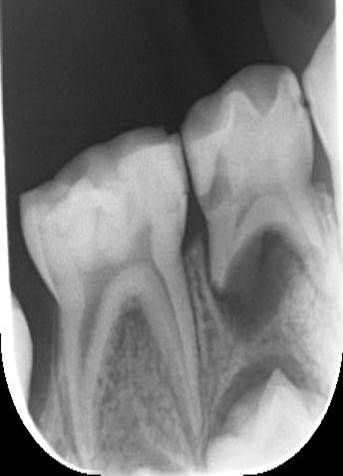

根管治療を行い、半年後のレントゲン写真です。根尖部のエックス線透過像が改善されました。

歯肉膿瘍があれば全てが歯周病由来ではありません。根管由来の病変、歯周病由来の病変、またはその両方を組み合わせたものが考えられます。

また、口内炎、腫瘍等も考えられますので、ご相談なさってください。